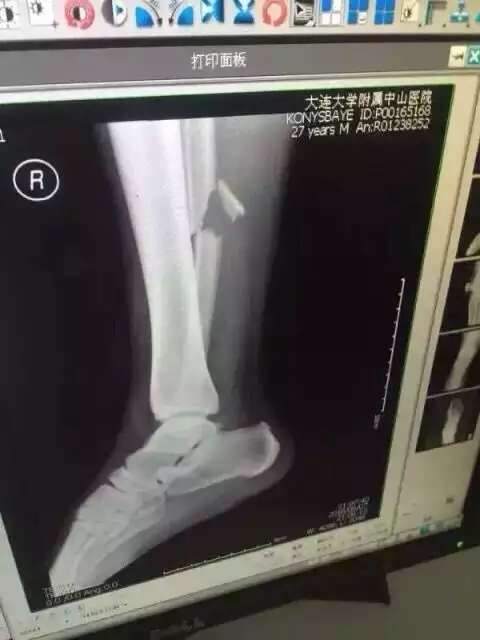

Полузащитник сборной Казахстана по футболу Улан Конысбаев, перенесший операцию после тяжелой травмы ноги, полученной во время товарищеского матча, пробудет в Китае еще семь дней, сообщают Vesti.kz.

Напомним, футболист получил травму в конце первого тайма матча против сборной Китая, неудачно приземлившись на ногу. В результате полученного перелома у него были порваны боковые связки и связки между малой и берцовой костью. Операция длилась 3,5 часа. По словам врачей, все прошло нормально. Отмечается, что Конысбаев сможет ходить только через три месяца. При этом некоторые шурупы в ноге полузащитника уберут почти через год.